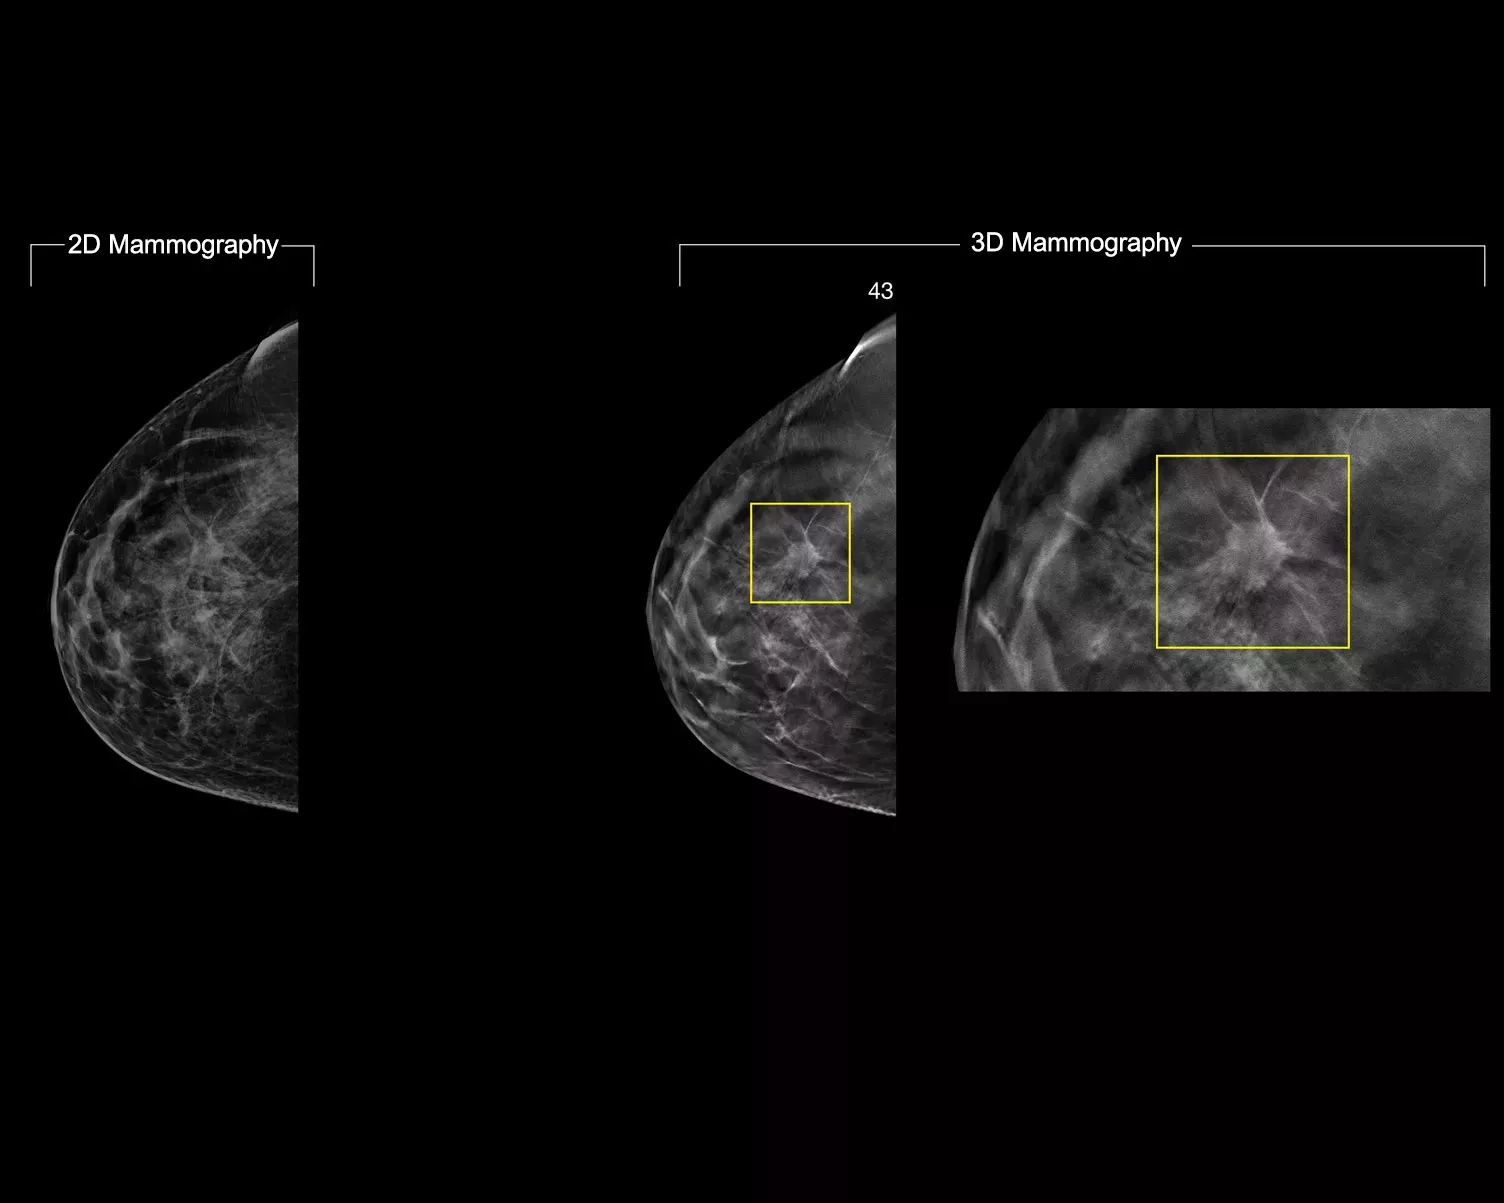

Image Gallery3

In a constantly changing clinical mammography environment, the flexibility and compatibility of ImageChecker 2D CAD Technology provides detection for conventional 2D images, as well as C-View™ and Intelligent 2D™ synthesised images derived from a tomosynthesis dataset.

ImageChecker 2D CAD Technology searches digital mammograms for potential microcalcifications and masses, characteristics commonly associated with breast cancer.